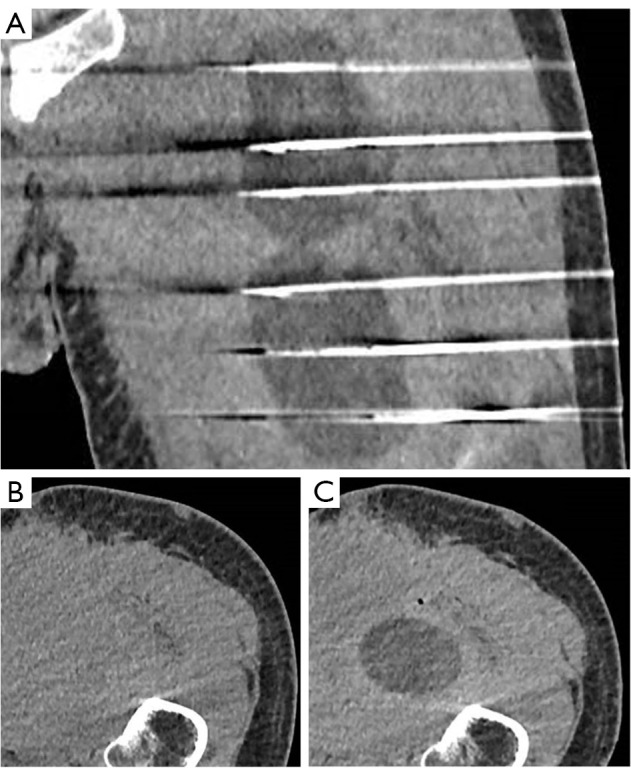

背景:转移性低分化脂肪肉瘤(DDLPS)主要采用化疗,但反应率较低。放疗和经皮冷冻消融等局部疗法可缓解无法手术的转移性肉瘤。在极少数情况下,这些消融疗法可使未经治疗的转移瘤在免疫介导下消退,这一过程被称为 "腹水效应"(abscopal effect)。随着免疫疗法的应用越来越广泛,近十年来关于腹水效应的报道也越来越频繁:病例描述:一名 55 岁的患者被诊断为 DDLPS IV 期,既往无病史。患者首先接受了诱导化疗,随后接受了整体切除术和辅助放疗。经过两次局部化疗复发后,患者出现了全身性疾病进展。在接受免疫化疗的同时,患者接受了姑息性经皮冷冻消融术。术后三个月,18氟脱氧葡萄糖正电子发射断层扫描/计算机断层扫描(18FDG PET/CT)显示,在冷冻消融肿瘤消退的同时,远处转移灶也出现了消退,这表明存在缺席效应:结论:在疾病进展后出现腹膜后效应,表明冷冻消融引发了全身免疫反应,凸显了这种治疗组合的潜力。然而,这仍是一种罕见现象,需要进一步研究和临床试验来确定最佳治疗顺序。

Case description: A 55-year-old patient with no prior medical history was diagnosed with a stage IV DDLPS. The patient was first treated with induction chemotherapy followed by en bloc resection and adjuvant radiotherapy. After two local relapses treated with chemotherapy, the patient developed a systemic disease progression. While progressing on immunochemotherapy, the patient underwent palliative percutaneous cryoablation. Three months after the procedure, the 18fluorodeoxyglucose positron emission tomography/computed tomography (18FDG PET/CT) showed regression of the distant metastasis alongside the regression of the cryoablated tumor, suggesting an abscopal effect.